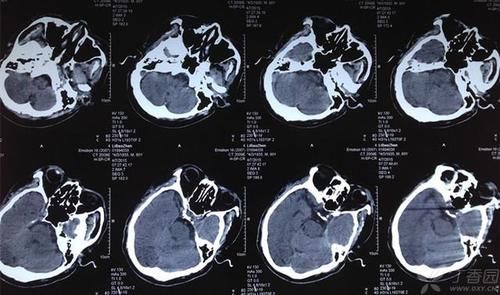

导语:一位72岁的老人,下午就被急诊接到了医院中,今年72岁的刘大爷,因为自己随便服药,把自己吃出了脑出血。

刘大爷的这个做法就是出现脑出血的最大原因,在换药的时候,血压就已经得不到控制,就会出现脑出血的问题。

临床上发生脑出血时,就是因为突然发病,而且因为突然发病,往往让患者和家人措手不及,正因为发病的快速,就会耽误抢救时间。